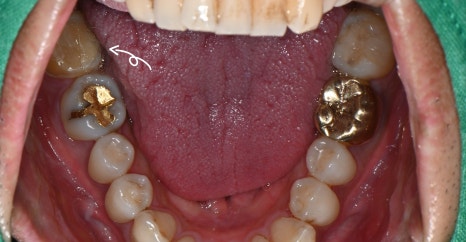

내원 당시 파노라마 사진 및 구강내 사진

30대 남성 환자분은 “찬물을 마실 때 오른쪽 아래 어금니가 시려요”라는 증상으로 내원하셨습니다.

큰 통증은 없었지만, 일상생활 중 불편함이 반복되어 정확한 진단을 받고 싶다고 하셨어요.